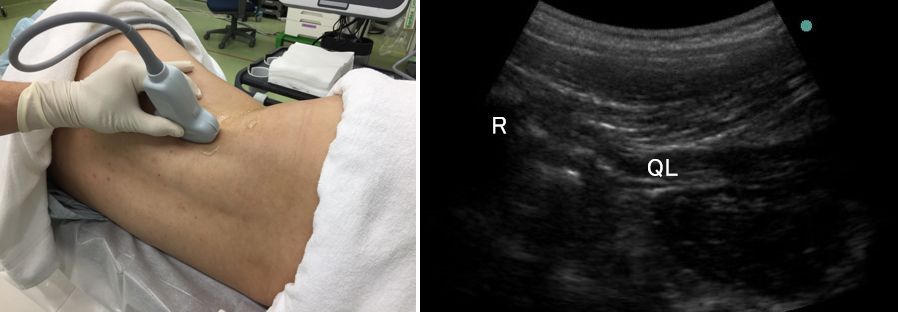

(3)ここで、腰方形筋を画像の中心に据えながら、プローブを回転させましょう。

これまでは、腰方形筋の横断面をみていましたが、縦断面がでるようにします。

このプローブの位置が、ちょうどL2の高さとなり、頭側の端に第12肋骨が見えます。

論文の絵のように、腎臓が見えなくてもかまいません。

腎臓を描出しようとすると、腰方形筋が見えにくくなりがちです。

腎臓にはこだわらない方がいいです。

腰方形筋の縦断面が描出できたら、論文の絵にあるように穿刺をしていきます。